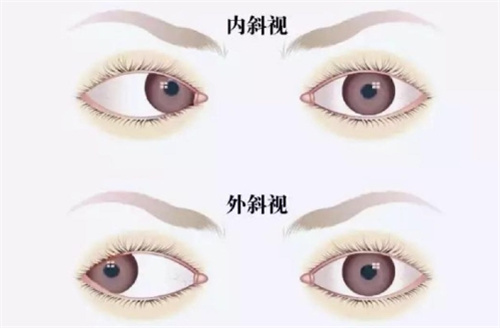

近视+散光(散光≤600度)

对夜间视力要求较高者

散光患者:

优先考虑TICL(3.16万元起),避免二次手术。